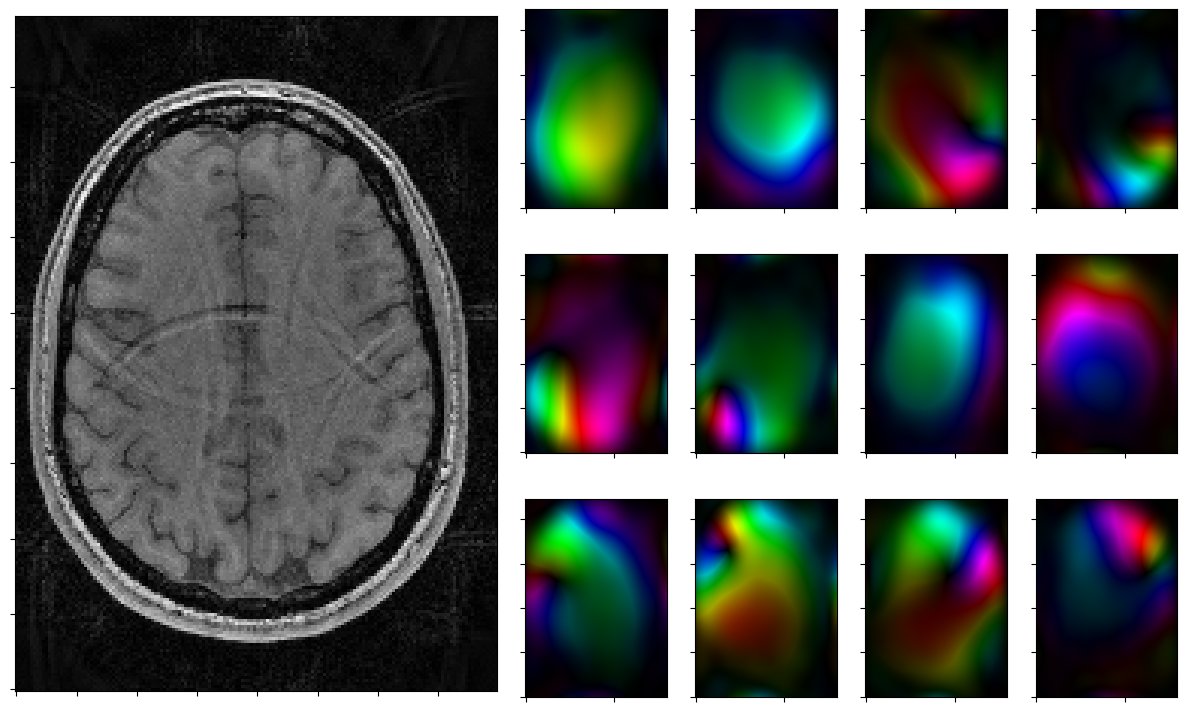

Run solver by hand and plot iterates

Run the solver iteratively and plot each step.

[12]:

for reco, reco_data in solver.while_(stoprule):

rho, coils = smoother.codomain.split(smoother(reco))

#rho, coils = normalize(rho,coils)

fig = plt.figure(figsize = (15,9))

gs = fig.add_gridspec(3,7)

axs = [fig.add_subplot(gs[0:3, 0:3])]

axs[0].imshow(np.abs(rho),cmap=mplib.colormaps['Greys_r'],origin='lower')

axs[0].xaxis.set_ticklabels([])

axs[0].yaxis.set_ticklabels([])

for j in range(3):

for k in range(3,7):

axs.append(fig.add_subplot(gs[j,k]))

axs[-1].xaxis.set_ticklabels([])

axs[-1].yaxis.set_ticklabels([])

for j in range(nrcoils):

axs[1+j].imshow(complex_to_rgb(coils[j,:,:]),origin='lower')

plt.show()

2026-01-29 15:10:09,152 INFO     CountIterations      :: it. 1>=5

2026-01-29 15:10:09,309 INFO     CombineRules         :: it. 0>=1000 | ((rel X:--(x=0)! | rel Y:--(y=0) ) & kappa:1.0e+00) | it. 0>=1000

2026-01-29 15:10:09,478 INFO     CombineRules         :: it. 1>=1000 | ((rel X:3.2e+01>=2.5e-01  | rel Y:3.1e+00>=2.5e-01 ) & kappa:1.1e+00) | it. 1>=1000

2026-01-29 15:10:09,618 INFO     CombineRules         :: it. 2>=1000 | ((rel X:1.2e+01>=2.5e-01  | rel Y:1.5e+00>=2.5e-01 ) & kappa:1.3e+00) | it. 2>=1000

2026-01-29 15:10:09,868 INFO     CombineRules         :: it. 3>=1000 | ((rel X:7.0e+00>=2.5e-01  | rel Y:9.3e-01>=2.5e-01 ) & kappa:1.7e+00) | it. 3>=1000

2026-01-29 15:10:10,029 INFO     CombineRules         :: it. 4>=1000 | ((rel X:4.6e+00>=2.5e-01  | rel Y:6.8e-01>=2.5e-01 ) & kappa:2.2e+00) | it. 4>=1000

2026-01-29 15:10:10,224 INFO     CombineRules         :: it. 5>=1000 | ((rel X:3.1e+00>=2.5e-01  | rel Y:5.0e-01>=2.5e-01 ) & kappa:2.2e+00) | it. 5>=1000

2026-01-29 15:10:10,380 INFO     CombineRules         :: it. 6>=1000 | ((rel X:2.2e+00>=2.5e-01  | rel Y:3.7e-01>=2.5e-01 ) & kappa:2.3e+00) | it. 6>=1000

2026-01-29 15:10:10,539 INFO     CombineRules         :: it. 7>=1000 | ((rel X:1.6e+00>=2.5e-01  | rel Y:3.0e-01>=2.5e-01 ) & kappa:2.8e+00) | it. 7>=1000

2026-01-29 15:10:10,695 INFO     CombineRules         :: it. 8>=1000 | ((rel X:1.3e+00>=2.5e-01  | rel Y:2.5e-01>=2.5e-01 ) & kappa:3.6e+00) | it. 8>=1000

2026-01-29 15:10:10,893 INFO     CombineRules         :: it. 9>=1000 | ((rel X:1.1e+00>=2.5e-01  | rel Y:2.2e-01>=2.5e-01 [Rule RelTolYStop(0.3333333333333333) triggered.]) & kappa:4.6e+00[All rules triggered.]) | it. 9>=1000

../_images/notebooks_parallel_mri_21_3.png